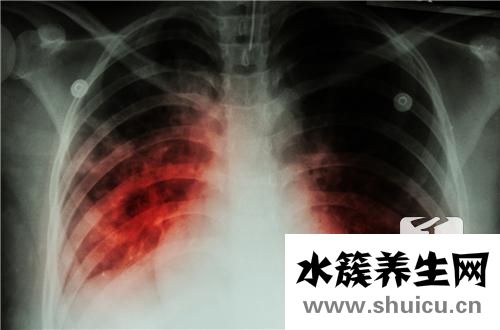

肺結(jié)核病是由結(jié)核病分枝桿菌感染肺臟造成的漫性傳染性疾病。是各種各樣結(jié)核病中最普遍者。我國(guó)完全免費(fèi)醫(yī)治肺結(jié)核應(yīng)該是永久性的,但我國(guó)完全免費(fèi)醫(yī)治肺結(jié)核并不是永久免費(fèi)的:

從上文大伙兒能夠 了解,患肺結(jié)核我國(guó)是有照料的,一般來(lái)說(shuō)治療費(fèi)也不會(huì)太價(jià)格昂貴,且如今肺結(jié)核是能夠 醫(yī)治的,病人無(wú)須擔(dān)憂還能人能活多久的問(wèn)題。

一般臨床醫(yī)學(xué)痊愈后,在抵抗能力好的狀況下,或不觸碰結(jié)核病患者,尤其是排菌的患者,一般不容易造成發(fā)作,醫(yī)好后跟平常人一樣,一樣能夠 健健康康。在臨床醫(yī)學(xué)痊愈后肺結(jié)核對(duì)日常生活影響并不大,建議以積極的心態(tài)看待日常生活,適度的提升健身運(yùn)動(dòng),增加抵抗力,防止呼吸系統(tǒng)感染。